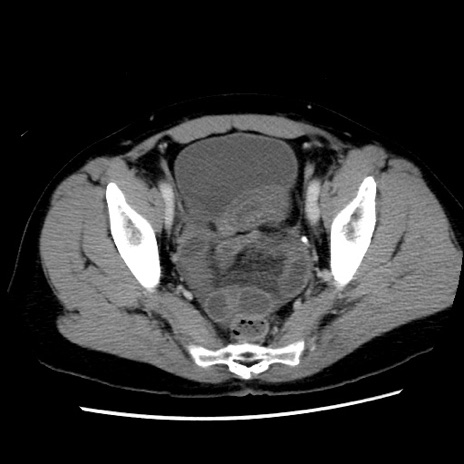

症例10(横断像)

【症例】 50歳代女性

【主訴】 腹痛

【現病歴】前日生レバーを食べた。今朝に排便あり。 昼前に突然発症の腹痛を生じ、当院救急外来を受診した。

【既往歴】 子宮筋腫にてで子宮全摘後

【身体所見】 意識清明、腹部:平坦、軟、下腹部やや左を中心に圧痛・反跳痛あり、筋性防御あり

【データ】WBC 7800、CRP 0.07